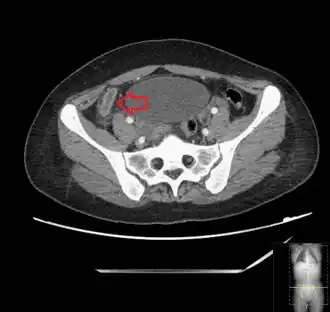

_(Radiopaedia_154713-127660_Axial_1).jpg.webp)

Diagnosis is based on a medical history (symptoms) and physical examination, which can be supported by an elevation of neutrophilic white blood cells and imaging studies if needed. Histories fall into two categories, typical and atypical.

In children the clinical examination is important to determine which children with abdominal pain should receive immediate surgical consultation and which should receive diagnostic imaging.[40] Because of the health risks of exposing children to radiation, ultrasound is the preferred first choice with CT scan being a legitimate follow-up if the ultrasound is inconclusive.[41][42][43] CT scan is more accurate than ultrasound for the diagnosis of appendicitis in adults and adolescents. CT scan has a sensitivity of 94%, specificity of 95%. Ultrasonography had an overall sensitivity of 86%, a specificity of 81%.[44]

Computed tomography

Where it is readily available, computed tomography (CT) has become frequently used, especially in people whose diagnosis is not obvious on history and physical examination. Concerns about radiation tend to limit use of CT in pregnant women and children, especially with the increasingly widespread usage of MRI.[49][50]

The accurate diagnosis of appendicitis is multi-tiered, with the size of the appendix having the strongest positive predictive value, while indirect features can either increase or decrease sensitivity and specificity. A size of over 6 mm is both 95% sensitive and specific for appendicitis.[51]

However, because the appendix can be filled with fecal material, causing intraluminal distention, this criterion has shown limited utility in more recent meta-analyses.[52] This is as opposed to ultrasound, in which the wall of the appendix can be more easily distinguished from intraluminal feces. In such scenarios, ancillary features such as increased wall enhancement as compared to adjacent bowel and inflammation of the surrounding fat, or fat stranding, can be supportive of the diagnosis. However, their absence does not preclude it. In severe cases with perforation, an adjacent phlegmon or abscess can be seen. Dense fluid layering in the pelvis can also result, related to either pus or enteric spillage. When patients are thin or younger, the relative absence of fat can make the appendix and surrounding fat stranding difficult to see.[52]